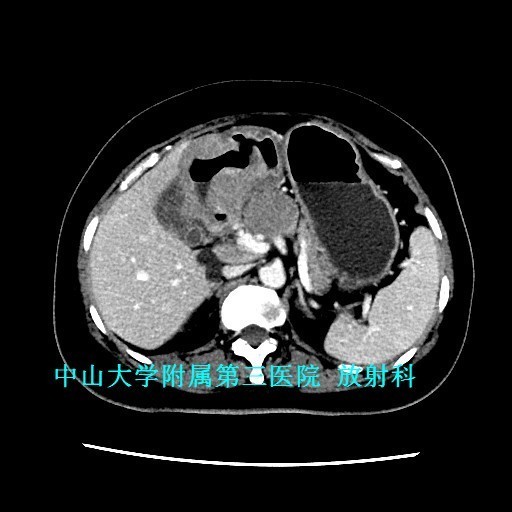

查体:腹软,上腹部轻压痛、无反跳痛,未触及包块。 辅查:1、胃镜:胃十二指肠恶性病变(待病理);2、上腹部CT:胃窦至十二指肠胃壁弥漫性增厚,考虑淋巴瘤可能性大。

讨论:原发性胃肠道淋巴瘤是一组起源于胃肠道黏膜下层淋巴组织的恶性肿瘤,成人较少见,约占胃肠道恶性肿瘤的1~4% 。影像表现具有一定特征性:弥漫性或局限性胃壁增厚是胃淋巴瘤主要特征,增厚的胃壁内缘呈波浪样或分叶状,外缘较光整,胃腔有一定的扩张度,增强扫描动脉期呈轻中度强化,静脉期持续强化。主要与胃癌鉴别,胃癌也表现为胃壁增厚,但一般增厚无淋巴瘤明显,而且胃壁僵硬,官腔变窄,常有浸润周围组织器官。 参考文献:侯明杰,齐鹏飞,高万勤等.原发胃肠道淋巴瘤的影像表现和误诊分析[J].实用放射学杂志,2014,(12):2112-2113,2121.